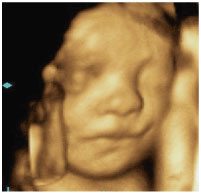

4Dエコーとは、3Dエコーに時間の要素を加えたものです。従来の2Dエコーでは断面的にしか見えなかった赤ちゃんの画像が、4Dエコーを導入してからはリアルタイムで動画として抽出できるようになりました。

週数によってお腹の中の赤ちゃんの顔や手足の様子がはっきりとわかります。

4Dエコーで見た胎児の様子。

当院設置の4D映像です。